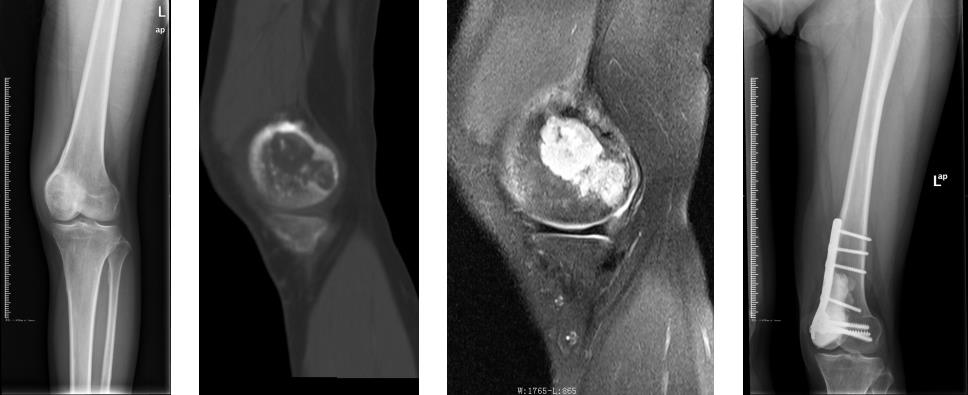

患者16岁(2008年)时因骨肉瘤(恶性)在我科治疗,现在肢体功能良好,并组建了幸福的家庭。

左股骨远端软骨肉瘤(恶性),在我科行保留关节的方式治疗,现关节功能良好,能跑能跳,上下楼梯自如。